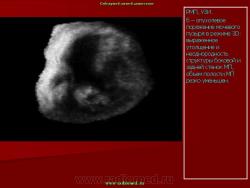

Внутриполостное ультразвуковое исследование в диагностике рака мочевого пузыря и предстательной железы.

Эндовезикальное сканирование позволяет дифференцировать все слои мочевого пузыря (Рис. 1). Между мышечной стенкой и слизистой оболочкой визуализируется гипоэхогенная подслизистая соединительная ткань. При стадии рака мочевого пузыря Та (инвазия в пределах слизистой) создается впечатление, что опухоль отделена от мышечной стенки мочевого пузыря, то есть подслизистый слой остается неизмененным (Рис. 2), также хорошо визуализируются устья мочеточников. При распространении инвазии субэпителиальной соединительной ткани (стадия Т1) опухоль уже непосредственно прилежит к мышечному слою, но не инвазирует последний (Рис. 3).